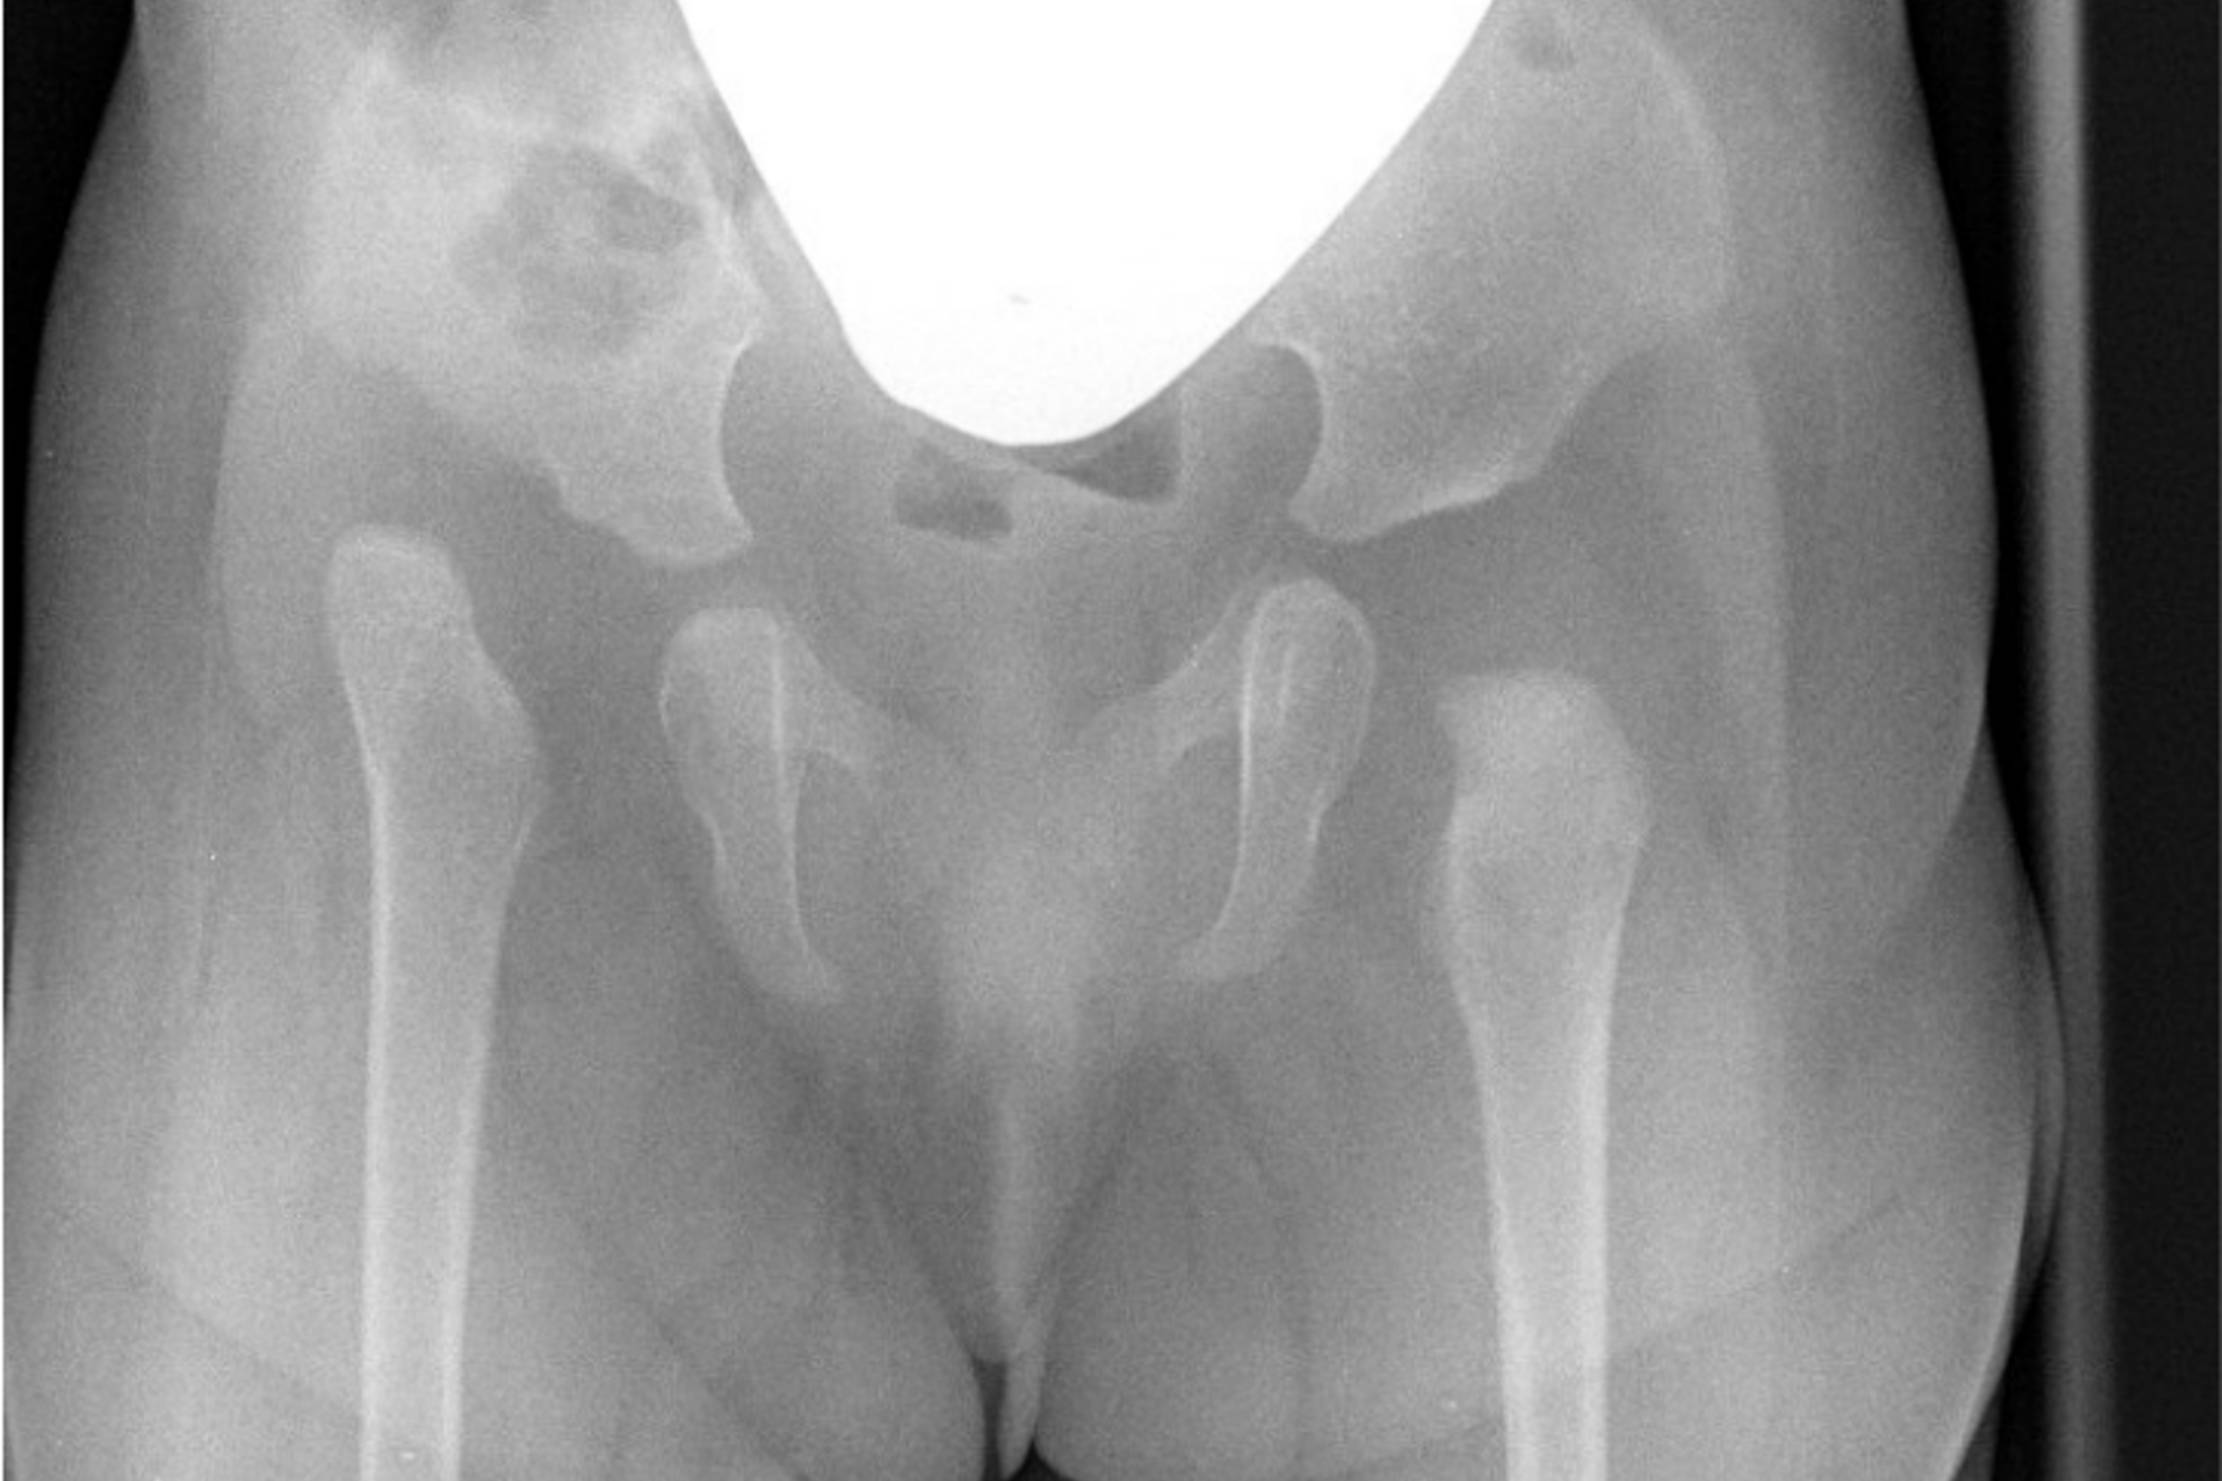

Ultraschall ist ein sicheres, schmerzloses, nebenwirkungsfreies Verfahren, das auch von kleinen Kindern sehr gut akzeptiert wird. Im Rahmen der U3-Untersuchung werden Hüftfehlstellungen (Hüftdysplasie oder Hüftluxation) erkannt, so dass sie zeitnah therapiert und größtenteils folgenfrei ausheilen können.

Manche Krankheitsbilder machen eine Röntgendiagnostik unumgänglich. Durch spezielle Kinderfilter wird die Strahlenbelastung für die kleinen Patienten minimiert.